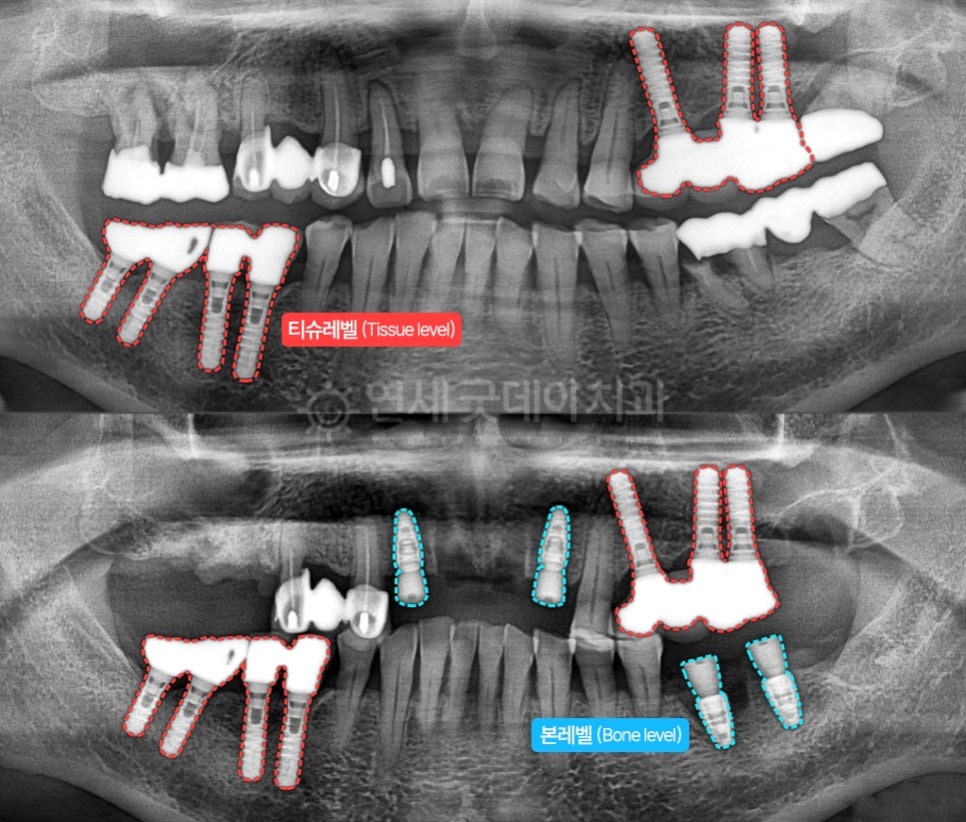

임플란트는 구조적인 형태에 따라

본레벨(Bone level)과

티슈레벨(tissue level)로 나뉩니다.

Bone은 잇몸뼈를 뜻하고

Tissue는 잇몸조직(=잇몸살)을 뜻하는 것입니다.

임플란트의 높이(level)가

잇몸뼈에서 끝나냐

잇몸조직에서 끝나냐에 따라

본레벨, 티슈레벨로 나뉘는 것입니다.

위 이미지에서 가장 오른쪽 1개만 본레벨

나머지 왼쪽 3개는 티슈레벨입니다.

씹는 힘이 쎈 환자분들은 티슈레벨을

잇몸뼈가 푸석푸석하거나

치조골 안팎의 높낮이 차이가 많이 날 경우,

혹은 앞니부위일 경우 본레벨을 사용하고 있습니다.

파란색 – 본레벨(Bone level)

빨간색 – 티슈레벨(Tissue level)

본원의 스트라우만 임플란트 시술증례